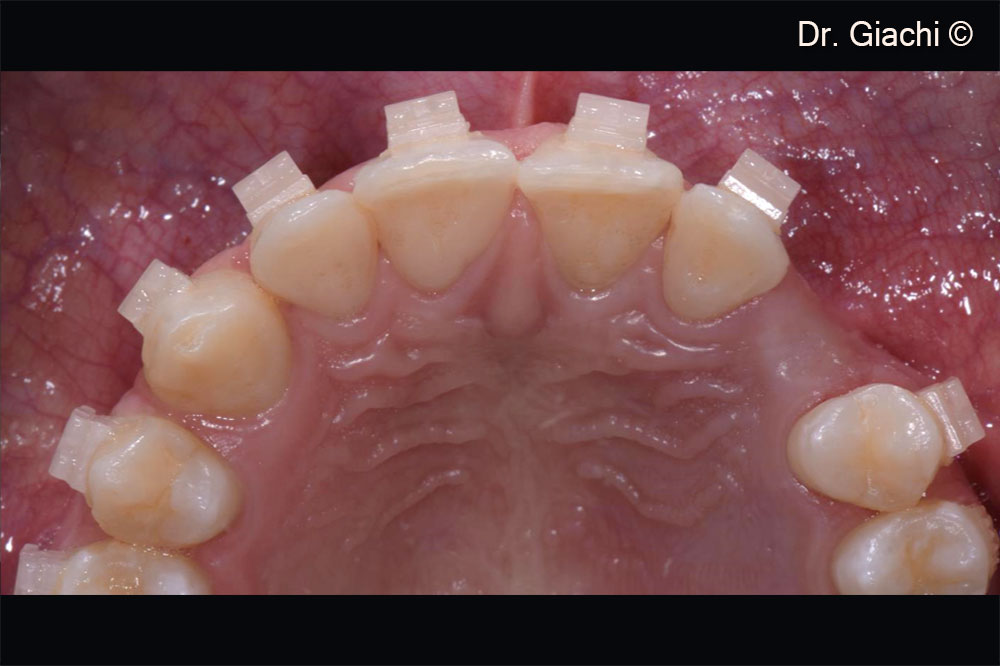

Một bệnh nhân nam (16 tuổi) có răng nanh trên không thể phục hồi bằng phương pháp chỉnh nha truyền thống.